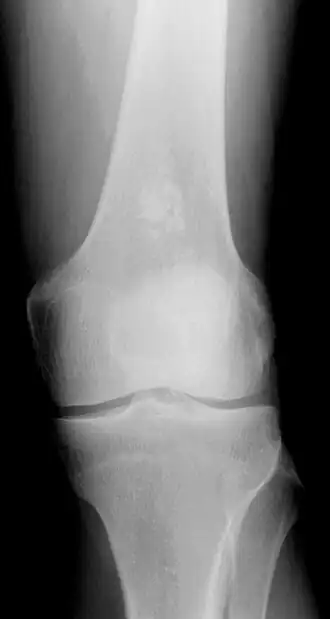

Encondroma do fêmur.

Em uma radiografia é visto como um osso aumentado, com maior radiotransparência, calcificações nodulares e menores que 3 cm. Fora das falanges fazem calcificações em anel ou em arco. Assemelha-se ao condrossarcoma de baixo grau devido à hipercelularidade, binucleação e alteração do mixoide, mas condromas são indolores e crescem muito mais lentamente. [4]

Mais frequentemente encontrados nos ossos das mãos e pés, e menos comumente encontrados no fêmur, úmero ou tíbia. Mais comuns entre os 20 e 50 anos, descobertos acidentalmente em uma radiografia. Afeta homens e mulheres com a mesma frequência.[5]